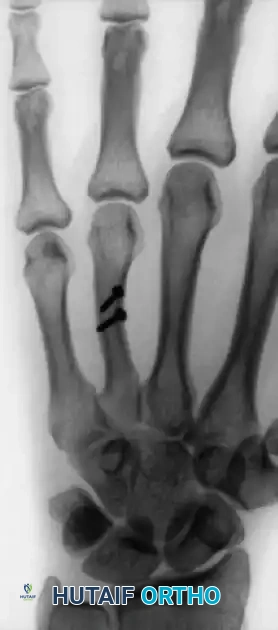

Oblique and Spiral Metacarpal Fractures

Oblique fractures of the metacarpal shaft often result in shortening and malrotation. While closed pinning (transverse or intramedullary) is an option, the lag screw technique provides superior interfragmentary compression for long oblique fractures where the fracture length is at least twice the diameter of the bone.

Alternative pinning configurations for metacarpal shaft fractures: